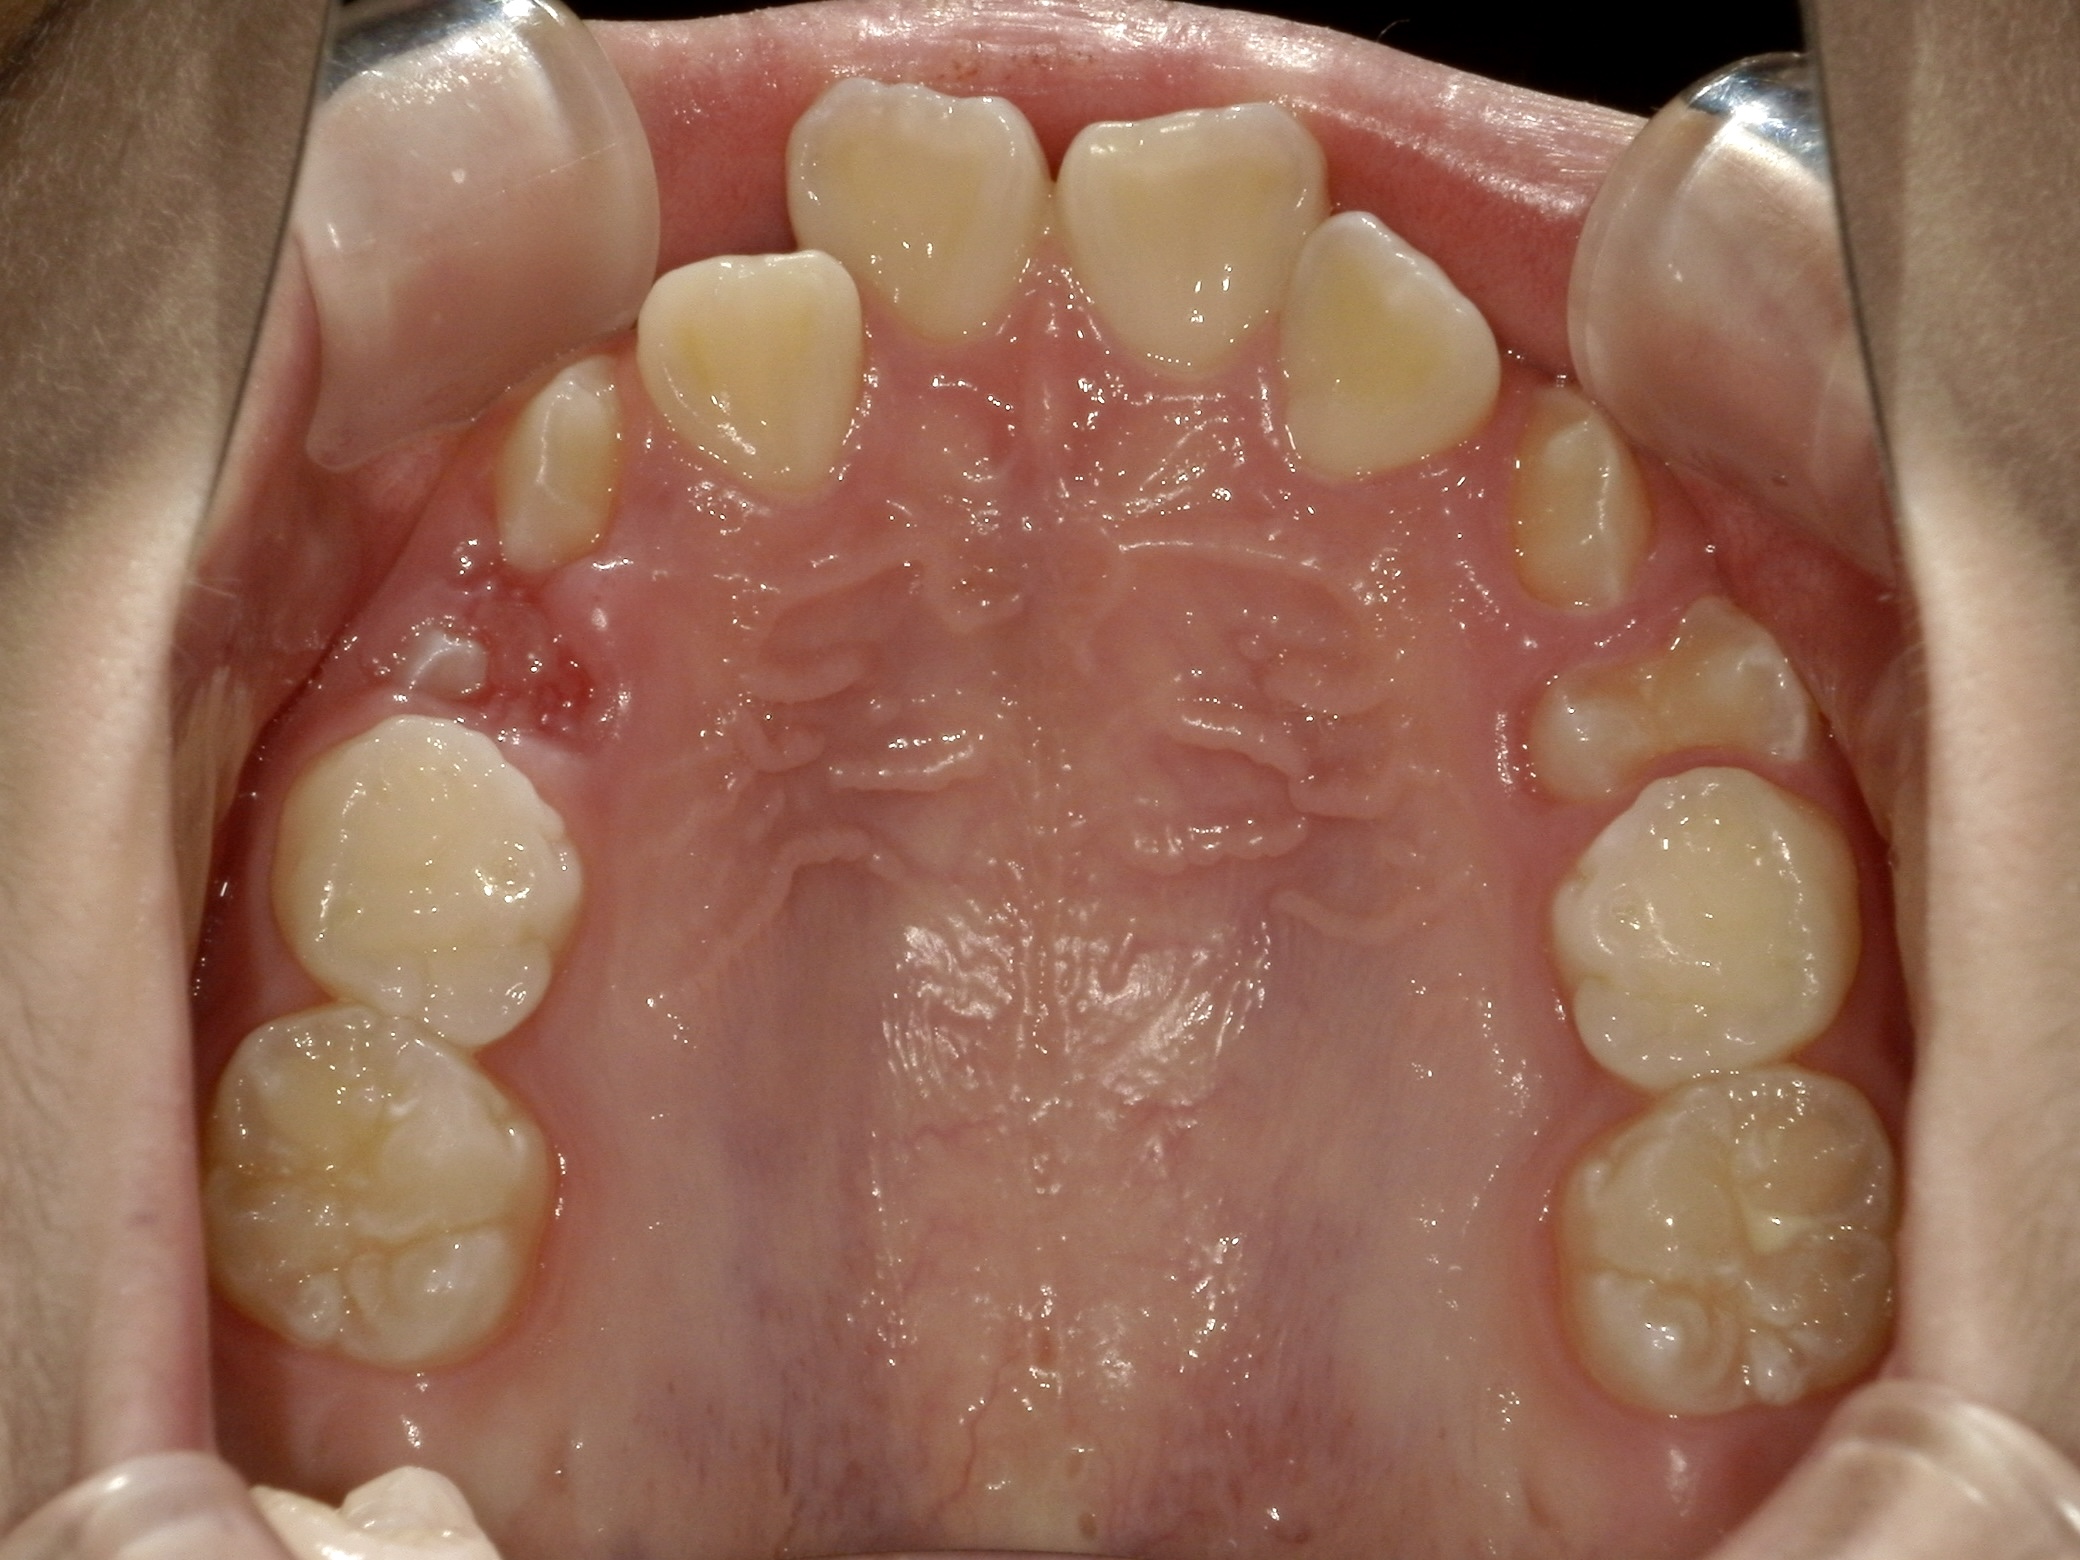

治療前/上の歯だけの状態

一番前の歯が特に出ているのがわかります。 -